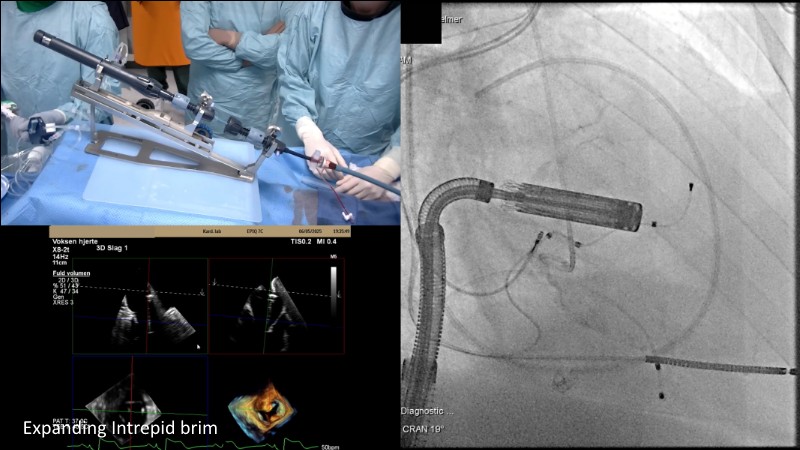

This EuroPCR 2025 session highlights the evolving role of transcatheter mitral valve replacement, focusing on the clinical potential of mitral regurgitation elimination. Get an overview of the current status of the Intrepid TMVR programme, learn about the transition to the 29Fr transfemoral system, and explore how patient screening—especially in the presence of mitral annular calcification—impacts procedural planning. Real-world case reviews from the APOLLO-EU trial offer practical insights into how this next-generation system is being applied in Europe today.